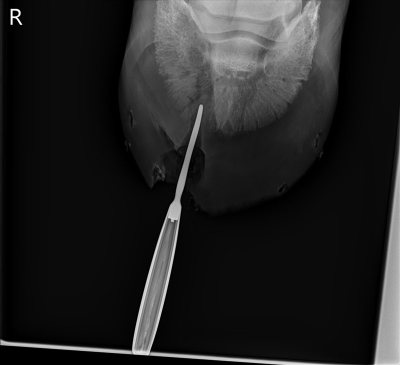

![]() |

| X-ray taken during surgery with a probe inserted to confirm that they were headed in the right direction. |

| Side view of same. |